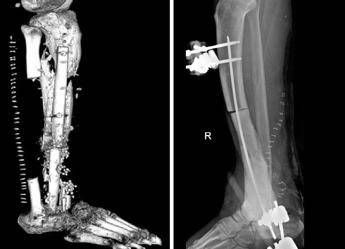

I medici hanno ricostruito al giovane, di origini nigeriane, intere parti di ossa, muscoli e pelle. Le operazioni hanno avuto successo. A distanza di 1 mese Onya cammina con le stampelle e vive in una casa famiglia, assistito dai servizi sociali. Emigrato dalla Nigeria e approdato sulle coste della Calabria nel 2017, Onya è stato accolto in Italia e dopo qualche mese gli è stato offerto un lavoro da operatore ecologico in una città del Lazio, raccontano dal Gemelli. L'inizio di una nuova vita, spezzata sul nascere da un incidente. Mentre andava a lavorare, il giovane finisce con la gamba destra dentro una buca coperta da un compensato di legno e riporta una brutta ferita. Per lui inizia un'odissea tra vari ospedali: visite, interventi parziali e tanti antibiotici, finché Onya arriva al Pronto soccorso del Gemelli. La diagnosi è di osteomielite post-traumatica, una grave infezione ossea che coinvolgeva gran parte della tibia e della caviglia della gamba destra, contratta a seguito di quel trauma iniziale apparentemente banale e causata – come rileveranno i tamponi colturali profondi – da una serie di batteri mangia-carne (flesh-eating): dallo Stafilococco aureus all'Escherichia coli, passando per tanti altri, che in pochi mesi avevano devastato la cute e i muscoli del giovane, fino a intaccare l'osso. In casi come questi gli antibiotici non bastano più, serve la chirurgia per rimuovere le parti infette e l'ampuazione e un pericolo concreto. Onya però non ne vuole sapere. I medici provano a convincerlo, ma lui è irremovibile e così l'ortopedico Carlo Perisano e la chirurga plastica Elisabetta Pataia gli propongono una soluzione alternativa: proveranno a rimuovere tutta l'infezione, che significa asportare la parte inferiore della gamba e parte della caviglia, per poi ricostruire il tutto. "Una vera e propria impresa durata circa 1 anno" con "vari interventi, mai descritta prima in letteratura – si legge in una nota – che ha restituito a Onya la sua gamba". Spiega Perisano, ricercatore in Ortopedia e Traumatologia all'Università Cattolica del Sacro Cuore e dirigente medico presso la Uoc di Ortopedia e Traumatologia della Fondazione Policlinico universitario Agostino Gemelli Irccs: "In una prima fase abbiamo resecato quasi tutta la tibia del paziente sotto il ginocchio e l'astragalo, per rimuovere tutti i focolai di infezione. Successivamente abbiamo messo un sostituto temporaneo dell'osso, cioè uno spaziatore cementato e antibiotato, al fine di far guarire i tessuti e ridurre il rischio di re-infezione. Dopo 4 mesi di terapia antibiotica, abbiamo iniziato un percorso di ricostruzione ossea". Inizialmente è stato fatto un tentativo di allungamento dell'arto con un fissatore esterno. "Si tratta di un intervento particolare – descrive l'ortopedico – consistente nell'osteotomia della parte di tibia rimanente e nella distrazione dei 2 monconi ossei (il gap osseo era di circa 20 cm), per permettere all'osso neoformato di crescere tra le porzioni di osso residue. In questo modo abbiamo recuperato 10 centimetri di osso; tanti, ma non sufficienti a ricostruire la parte mancante di tibia". E' stato quindi necessario modificare la strategia chirurgica. Per dare un'adeguata copertura cutanea e permettere all'osso sottostante di rigenerarsi e guarire, l'équipe multidisciplinare di ortopedici e chirurghi plastici ha effettuato dunque un delicato intervento, definito come "del tutto inedito". Illustra Pataia, docente di Chirurgia ortoplastica in Cattolica e chirurgo plastico nella Uoc di Ortopedia e Traumatologia del Gemelli: "Abbiamo effettuato una ricostruzione complessa prelevando 3 lembi, un muscolo-cutaneo dalla coscia e 2 ossei da entrambi i peroni del paziente. Successivamente, questa sorta di patchwork osseo-muscolo-cutaneo è stato collegato con tecnica microchirurgica. Si tratta di un sistema detto 'lembo-chimera', che consiste nel collegare un lembo muscolo-cutaneo al vaso arterioso della gamba ricevente, per poi collegare tra di loro i restanti lembi. In pratica il primo lembo alimenta l'altro, attraverso una serie di connessioni vascolari realizzate al microscopio, che partendo da un solo vaso ha consentito di alimentare 3 lembi diversi". Utilizzando infine il perone della gamba sana e quello della gamba malata, Perisano ha ricostruito la parte mancante della tibia e l'astragalo del paziente, fissando il tutto con delle viti ortopediche e mettendo a protezione un fissatore esterno circolare, per permettere la guarigione dei tessuti e far consolidare le parti ossee. "Si tratta di un intervento eccezionale – commenta Giulio Maccauro, ordinario di Ortopedia alla Cattolica e direttore della Uoc di Ortopedia e Traumatologia del Gemelli – che conferma la validità della nostra intuizione di creare un servizio di chirurgia ortoplastica, interdisciplinare con ortopedici e chirurghi plastici, all'interno della nostra struttura di Ortopedia e Traumatologia. Si tratta di una disciplina nuova, che ha pochi altri centri in Italia". —cronacawebinfo@adnkronos.com (Web Info)